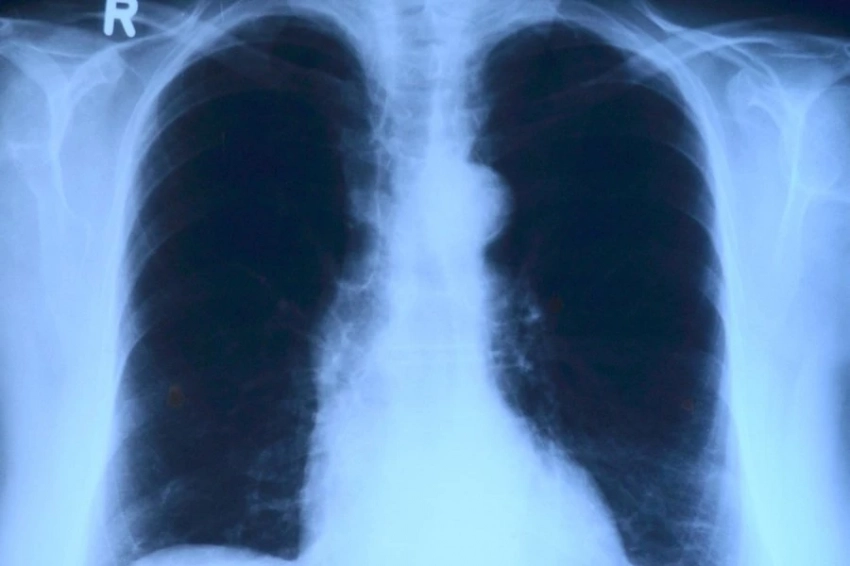

Ученые из Университета Эмори (США) научили ИИ определять риск развития диабета по рентгеновским снимкам. Результаты исследования опубликованы в журнале Nature Communications.

Модель ИИ была разработана на основе большого набора клинических данных, состоящего из более чем 270 000 рентгенограмм и 160 000 пациентов, и протестирована на проспективном наборе данных почти из 10 000 рентгенограмм. Результаты показали, что наша модель эффективно выявляла диабет 2 типа (T2D) с ROC AUC 0,84 и распространенностью 16%, помечая 14% как подозрительные на T2D. Внешняя проверка в географически удаленном учреждении показала, что ROC AUC составила 0,77, при этом у 5% пациентов впоследствии был диагностирован СД2. Кроме того, используя объяснимые методы искусственного интеллекта, мы выявили корреляции между специфическими признаками ожирения и высокой предсказуемостью, что свидетельствует о потенциале CXR для расширенного скрининга T2D.

ИИ предсказывал диабет точнее, чем простая модель, основанная только на клинических данных без изображений. В некоторых случаях рентген грудной клетки предупреждал о высоком риске диабета еще за три года до того, как пациенту ставился диагноз.